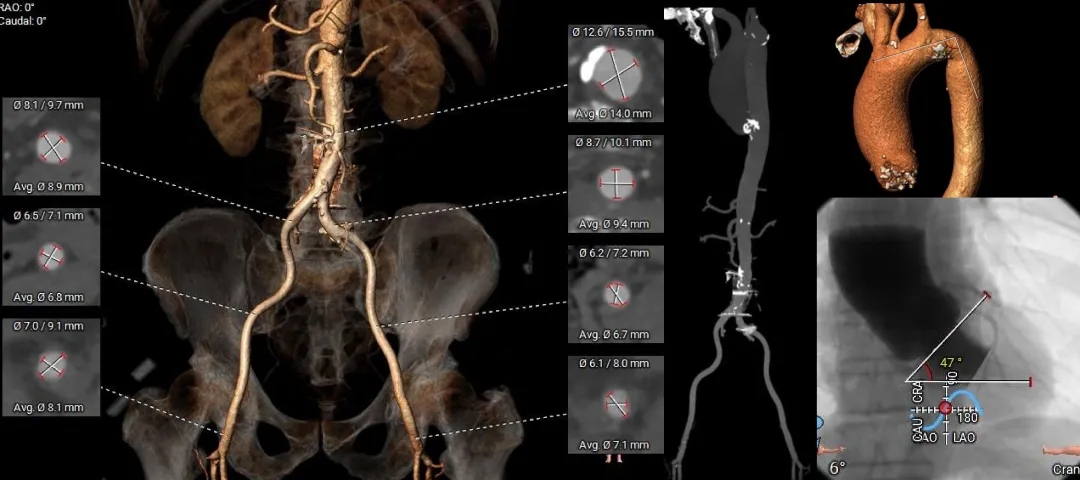

术前CT分析

-

TYPE-0型二叶瓣(纵列式),重度钙化,钙化分布不均匀,延伸至流出道可见,瓣叶明显增厚;

瓣环径约为24.0mm,流出道偏收口型,心室壁增厚,收缩期小心室;

左冠开口高度约为23.8mm,右冠开口高度约为27.0mm;

瓣环水平夹角47度,非横位心,升主动脉明显扩张;

外周入路走形轻度迂曲,左右股动脉直径尚可,主动脉弓部、腹主动脉处见少量钙化附着;

左侧下肢动脉入路最小平均内径6.7mm,右侧下肢动脉入路最小平均内径6.8mm。

主动脉根部测量

Annulus:24mm

LVOT:21.5mm

钙化积分:1396

SOV:30.6*43mm

STJ:41.9mm

AAO:51.2mm

瓣上结构测量

瓣上2mm

23.4mm

瓣上4mm

25.5mm

瓣上6mm

25.3mm

瓣上8mm

25mm

瓣上10mm

26.6mm

瓣上12mm

26.8mm

冠脉风险评估

LCA Height

RCA Height

左室测量

工作体位

双窦展开

左冠切线

外周入路评估